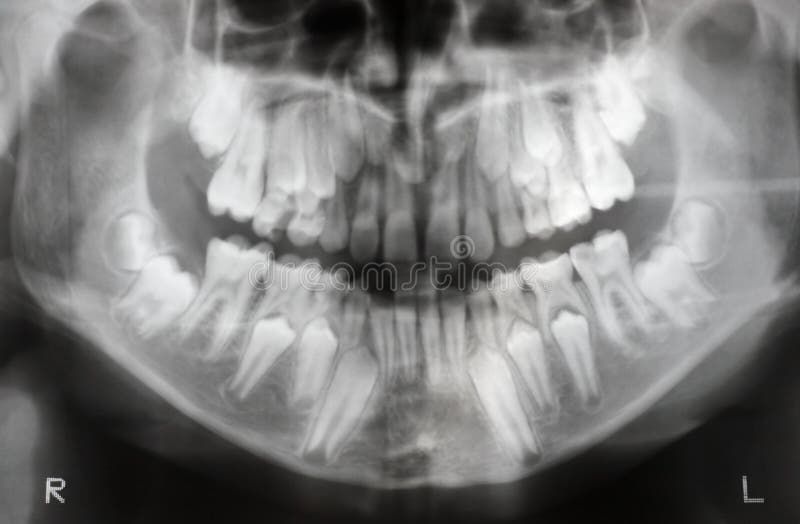

WebHay varios aspectos en los que fijarse: Color. Los dientes de leche son más blancos que los permanentes. Bordes. Los dientes de leche son suaves en la parte de abajo, mientras. WebAunque esta patología puede darse en los dientes de leche, suele ser más frecuente que suceda en los dientes permanentes o definitivos, siendo común en los. WebLa odontopediatría es el área de la odontología especializada en cuidar los dientes de los niños, tanto los temporales como los definitivos.. Al contrario de lo que. WebEn su boca estaban los 16 dientes de leche, ya había perdido los incisivos temporales inferiores, 10 arriba y 6 abajo. Y creciendo en sus encías para sustituirlos. WebEs sencillo, llama a Aguilar Dental Salut (934 151 113) y pide hora con la Odontopediatra. Te dará un diagnóstico después de hacerle una ortopantomografía para. WebEl Equipo Novasmile. 4 julio 2012. 599. Muchos adultos aún conservan los dientes de leche y se preguntan si los definitivos les saldrán alguna vez, si carecen de. WebEn esta nueva edición de #SabíasQué..., Jacobo nos explica algo que suele dar mucha curiosidad a los padres primerizos: la aparición de los dientes definitiv... WebLos dientes de leche tienen una capa de esmalte dental y es muy delgada, puesto que el trabajo de estos será menor. Además de que la permanencia de los. WebNormalmente a los 5 o 6 años empezamos a sustituir los dientes provisonales por los definitivos, sin embargo hay adultos que continúan durante años. WebRadiografia de los dientes de leche junio 27, 2022 admin . Radiografía de los dientes de un niño de 5 años “Dentro de cien años no importará cuál era mi cuenta.